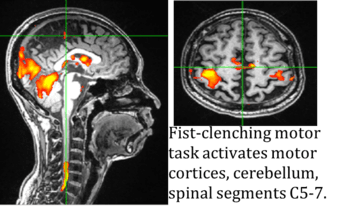

The Systems Neuroscience & Pain Laboratory at Stanford University (SNAPL) is actively recruiting a postdoctoral fellow who will join our research project on chronic pain. Funded by the National Institute of Health and directed by neuroscience professors Sean Mackey and Gary Glover, our goal is to investigate mechanisms of chronic pain using methods we developed to image the entire CNS via simultaneous spinal cord/brain fMRI.

Our plan is to characterize neurobiological mechanisms underlying chronic pain and use this information to develop objective biomarkers of pain, ultimately, to derive new personalized interventions. Given abundant findings that fMRI of the brain can act as biomarker for chronic pain conditions, we propose utilization of our simultaneous spinal cord/brain fMRI to develop biomarkers of pain severity. Our research can be categorized as follows:

● Multivariate pattern analysis of spinal cord/brain data for corticospinal biomarker,